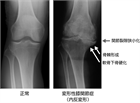

診断

1. 座位からの立ち上がり、歩行時、階段昇降時に疼痛が誘発される。進行し、関節腫脹が強い場合には、夜間痛などの安静時痛もみられるため、診察時に問診および観察する。